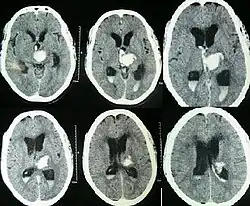

Tanto a angiografia por tomografia computadorizada (ATC) como a angiografia por ressonância magnética (ARM) demonstraram ser efetivas no diagnóstico de malformações vasculares intracranianas após a hemorragia intracerebral.[13] Com tanta frequência, um angiograma de tomografia computadorizada será realizado para excluir uma causa secundária de hemorragia[14] ou para detectar um "sinal local".

A hemorragia intraparenquimatosa pode ser reconhecida na tomografia computadorizada porque o sangue aparece mais brilhante do que outro tecido e é separado da mesa interna do crânio por tecido cerebral. O tecido que envolve um sangramento é muitas vezes menos denso do que o resto do cérebro por causa do edema e, portanto, aparece mais escuro na tomografia computadorizada.[14]

Quando devido à pressão arterial elevada, eles geralmente ocorrem no putâmen ou no tálamo (60%), no cérebro (20%), no cerebelo (13) ou na ponte (7%).[15]